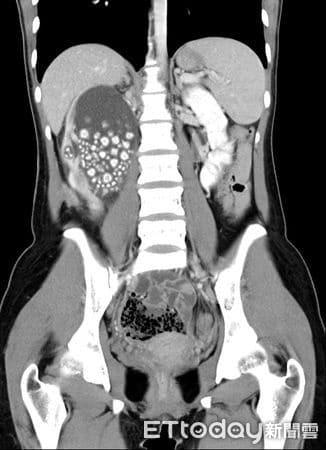

Η νεαρή γυναίκα άρχισε να νιώθει έντονη κόπωση, πυρετό και πόνους στη μέση. Οι γιατροί αρχικά υποψιάστηκαν λοίμωξη του ουροποιητικού ή φλεγμονή των νεφρών — καταστάσεις που αντιμετωπίζονται εύκολα. Όμως οι αξονικές και υπερηχογραφικές εξετάσεις αποκάλυψαν κάτι απίστευτο: το δεξί της νεφρό ήταν διογκωμένο και φραγμένο με εκατοντάδες πέτρες σαν μεγάλους κόκκους άμμου σχεδόν δύο εκατοστών.

Οι περισσότεροι ασθενείς έχουν έναν ή δύο πέτρες. Η νεαρή αυτή γυναίκα είχε εκατοντάδες, που συσσωρεύονταν επί χρόνια λόγω αφυδάτωσης, μέχρι που το σώμα της κατέρρευσε. Οι πέτρες είχαν μπλοκάρει το σύστημα διήθησης των νεφρών, προκαλώντας λοίμωξη και πυρετό.

Οι χειρουργοί του νοσοκομείου πραγματοποίησαν περκοτανοσκοπική νεφρολιθοτομή, μια ελάχιστα επεμβατική διαδικασία μέσω μικρής τομής στην πλάτη. Σε διάρκεια περίπου δύο ωρών, αφαίρεσαν περισσότερους από 300 πέτρες γεμίζοντας πολλούς ιατρικούς δίσκους.

Oι πέτρες που αφαιρέθηκαν από τα νεφρά της νεαρής κοπέλας

d7385546

H ακτινογραφία με τις πέτρες πάνω αριστερά